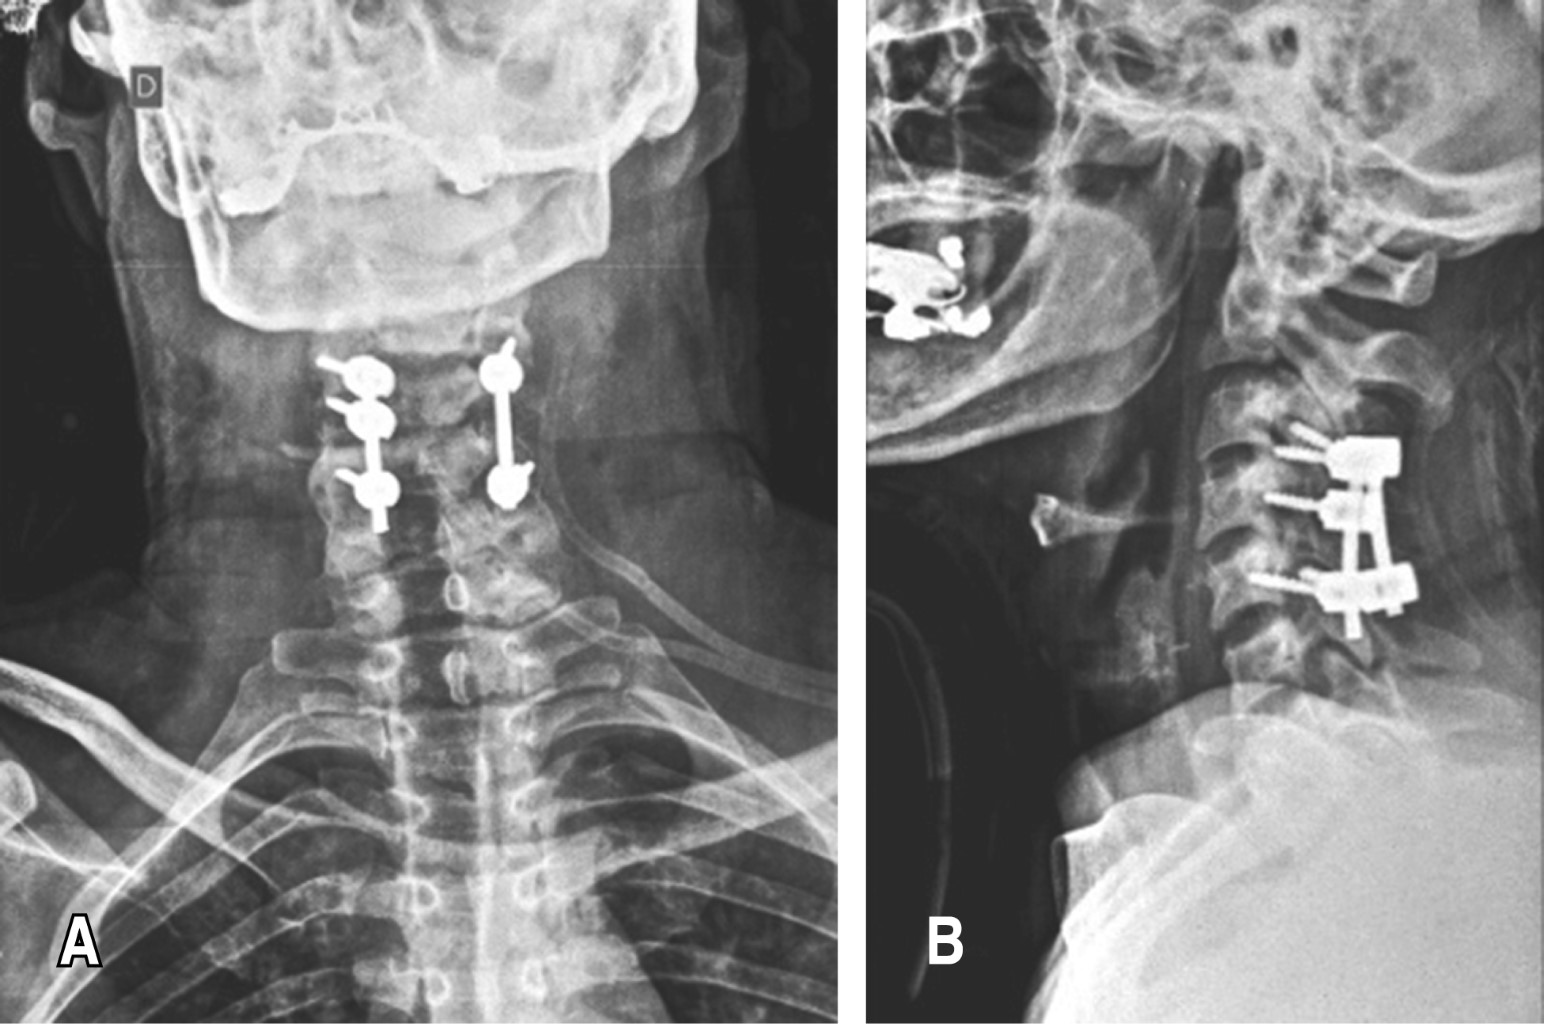

Se realiza toilette quirúrgica con fijación C3-C5 con tornillos facetarios y barras (Figura 3). El cultivo de colección y partes blandas dio positivo a Staphylococcus aureus meticilino sensible y el estudio de anatomía patológica la afectación ósea aguda. Continuó con vancomicina por seis meses con indicación de infectología, con buena evolución local.